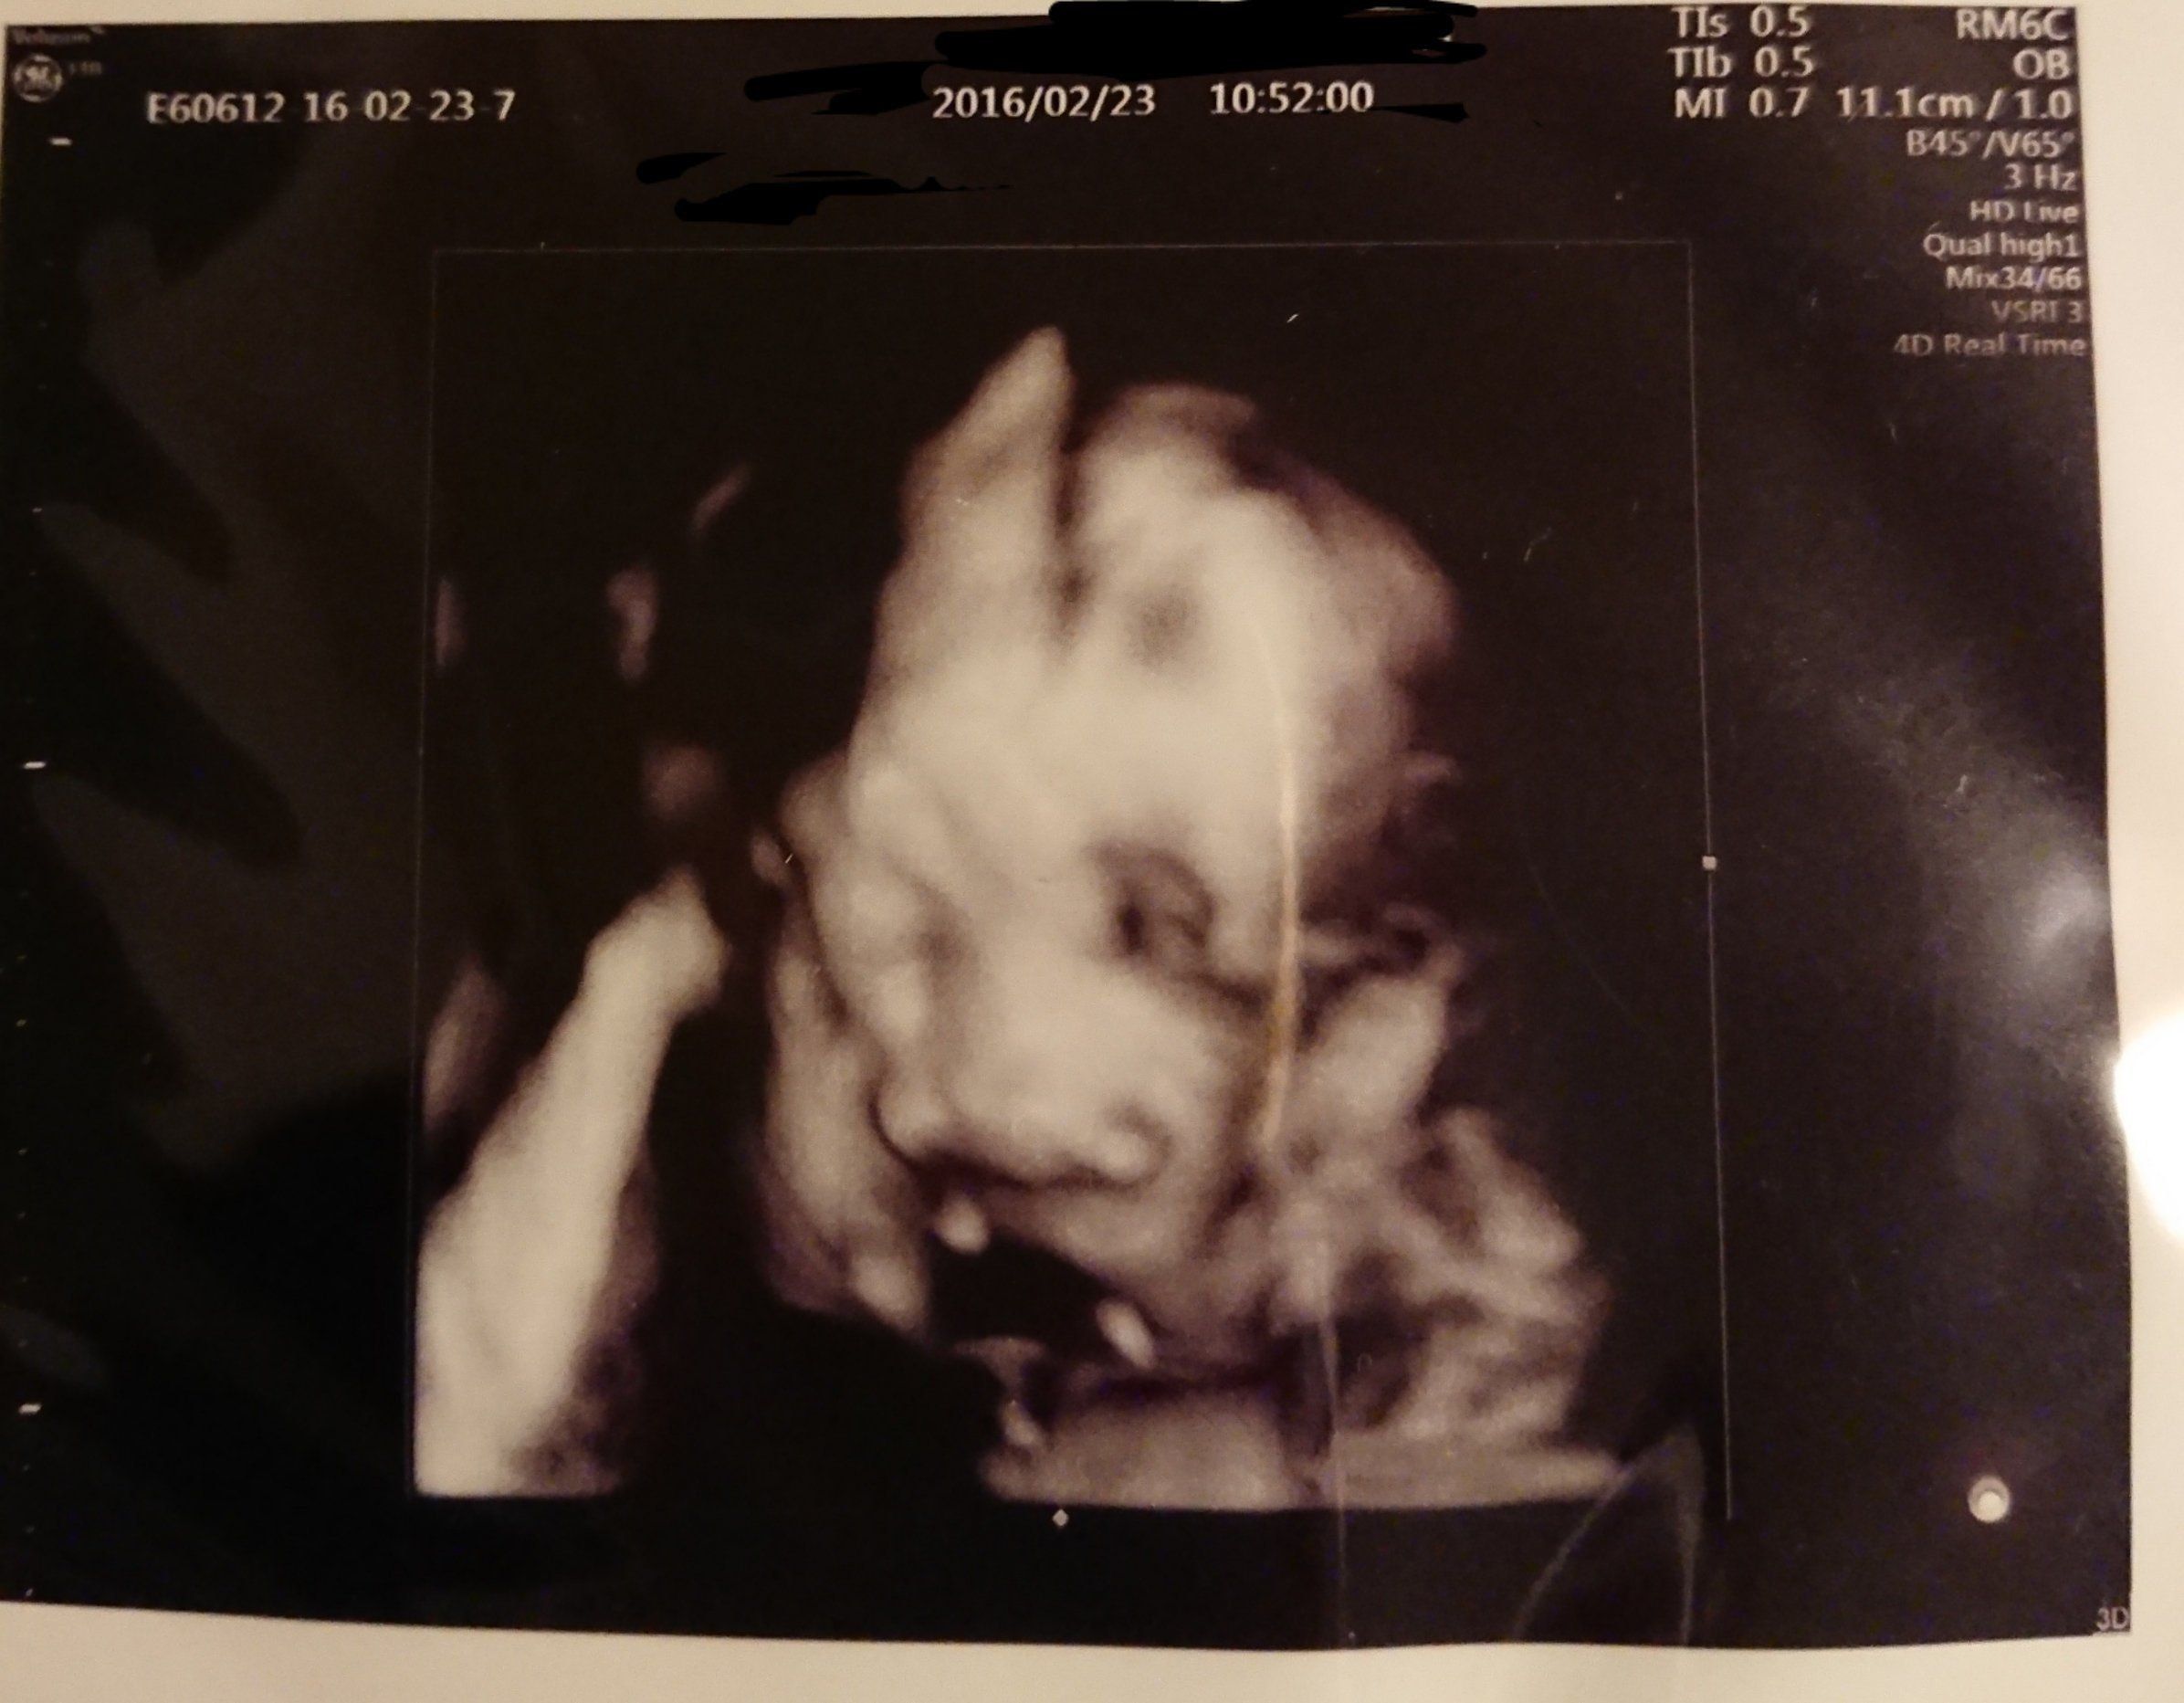

前回わからなかった性別がやっとわかりました。ドキドキして待っていると、先生が「女の子だよ! おしゃぶりの練習をしているのかな?」と。このエコー写真を見た時、突然ビビビッと感じ「メイ」と名付けようと決めました。

8ヶ月に入り、日に日に大きくなるお腹。胎動も激しくなり夜中に起きることも。仕事中に長時間立っているのがつらくなり、疲れやすくなってきました。赤ちゃんの顔がだいぶはっきりしているのが写真でわかります。